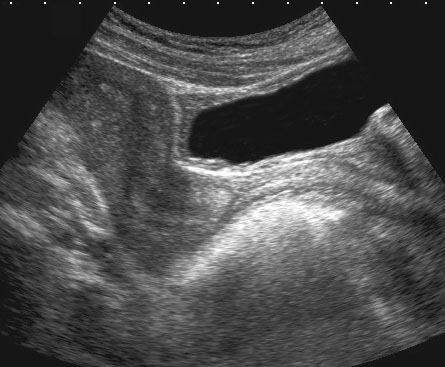

Bệnh lý của niệu đạo, âm đạo đoạn xa và cơ thắt hậu môn có thể được khảo sát bằng đầu dò âm đạo đặt ở vị trí âm hộ (mặt phẳng đứng dọc).

Hình ảnh

Giải phẫu siêu âm bình thường với đầu dò ở vị trí âm hộ